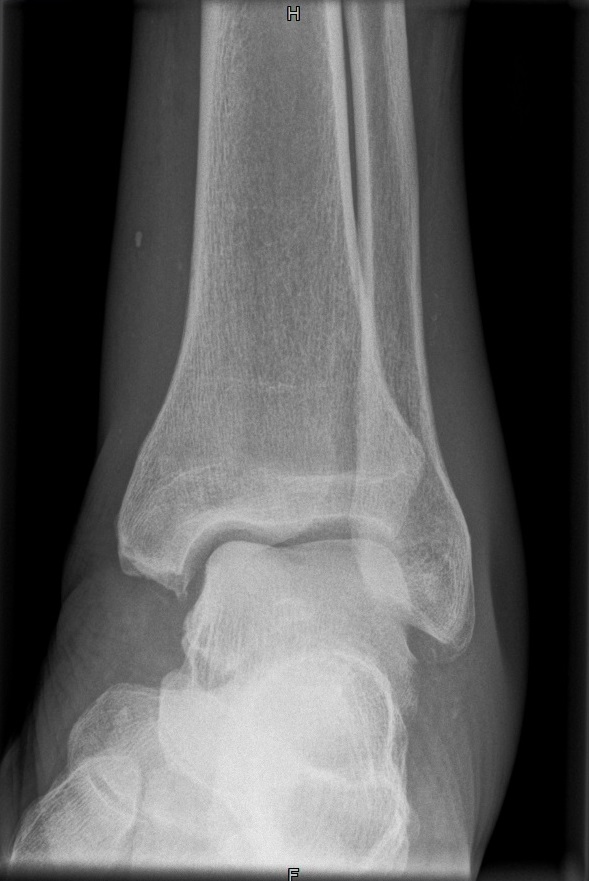

OSG seitlich

132_3.jpg

Fehler

Doppelkonturierung im vorderen Teil der Talusrolle. Die Fibula ist gegen dem Malleolus internus nach ventral verschoben. Die Längsachse des Talus ist verkürzt. Das untere Sprunggelenk kann nicht beurteilt werden.

Abhilfe

Keilkissen unter den Calcaneus legen bzw. Fuß flacher auf den Zehen auflegen lassen.